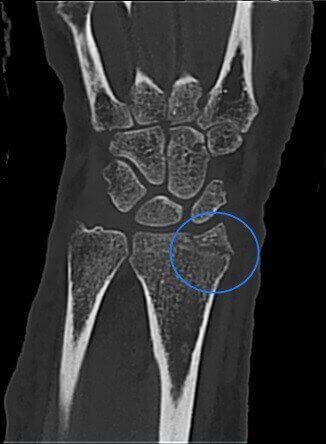

Fractura del proceso estiloides del radio.